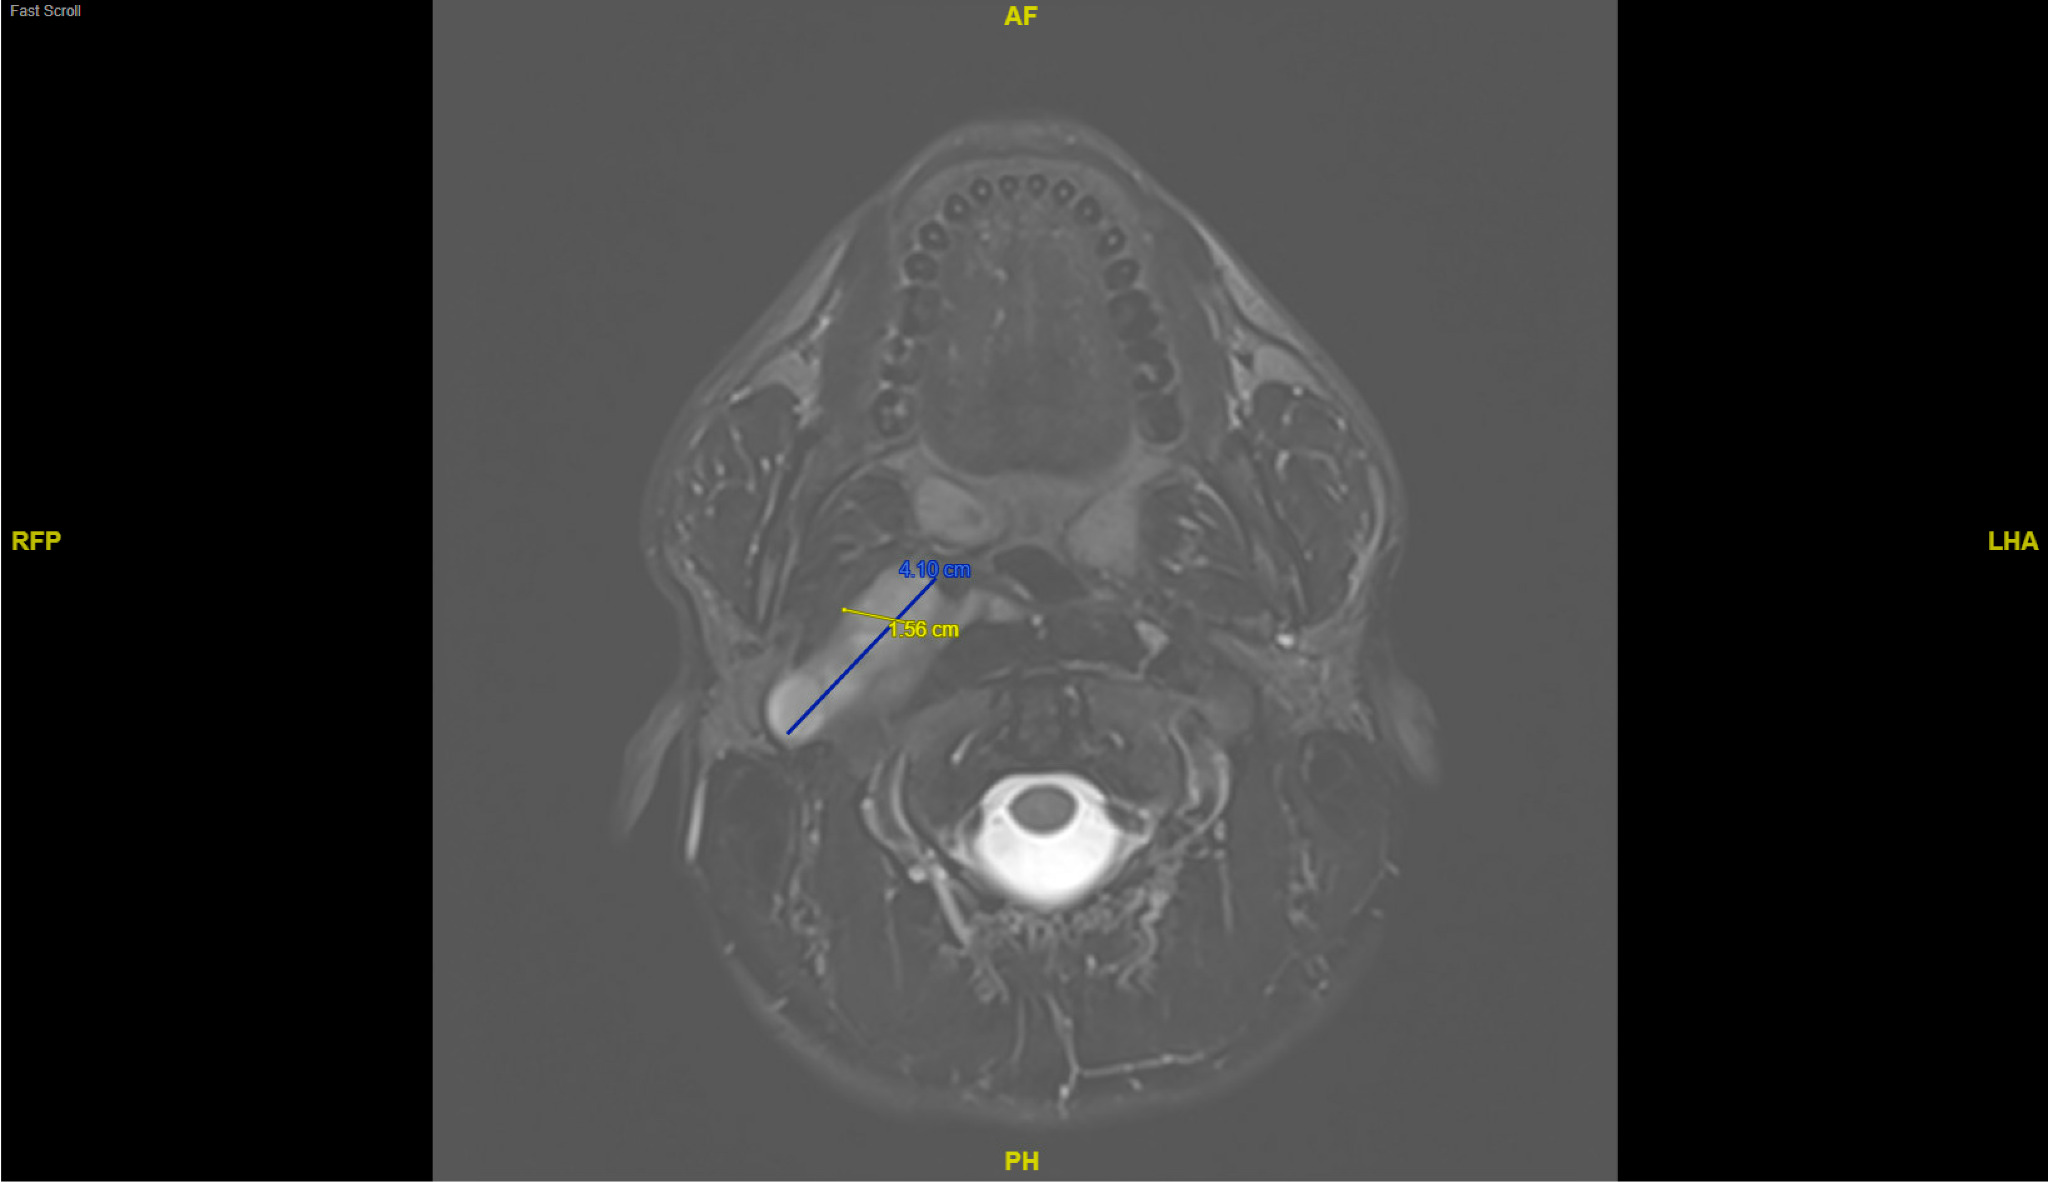

A 21-year-old previously healthy male presented with sudden-onset headache, photophobia, and neck pain accompanied by nausea and anxiety. Examination revealed right-sided neck tenderness to palpation and right-sided pain with active and passive movement. He had a normal cranial nerve and neurological exam without nuchal rigidity. Computerized tomography (CT) of the brain and neck showed a large cystic lesion in the carotid space (Figure 1). The lesion was further characterized with magnetic resonance imaging (MRI) that showed a 7.7 cm x 1.6 cm x 4.1 cm lobulated soft tissue mass involving the right carotid space with anterior displacement of the carotid artery. The lesion was isointense on T1-weighted imaging (T1WI), hyperintense on T2-weighted imaging (T2WI), and showed patchy internal enhancement concerning for a vagal nerve schwannoma (Figure 2).

Schwannomas are rare peripheral nerve tumors arising from the myelinating Schwann cells of the peripheral nervous system.1 Less frequently, they may impact cranial nerves. When affecting the vagus nerve, the patient may experience hoarseness or cough or may remain asymptomatic.2 Growth is usually limited to 2-3mm per year, and malignant transformation is possible but rare. Differential diagnosis of carotid space masses is broad but includes schwannoma of the vagus, glossopharyngeal, or spinal accessory nerves; congenital branchial cyst; paraganglioma; and infectious process.3,4 On MRI, paragangliomas usually show “salt and pepper” appearance due to flow voids, while branchial cleft cysts may show wall thickening, hypointensity on T1WI tending towards hyperintensity with infection or proteinaceous content, and variable intensity on T2WI.5,6 Schwannomas may appear cystic with isointensity on T1WI and hyperintensity on T2WI.1 Once schwannoma is suspected, the location of the internal carotid artery can provide diagnostic clues.7 Displacement of the internal carotid artery anteriorly away from the internal jugular vein is consistent with vagal nerve origin, and extension towards the jugular foramen of the skull further supports this diagnosis.2,7,8 Given encasement of upper cervical right internal carotid artery with anterior displacement, extension to the skull base, lack of internal flow voids disfavoring paraganglioma, and internal enhancement pattern disfavoring branchial cleft cyst, vagal nerve schwannoma was suspected and the patient was referred for surgical intervention.